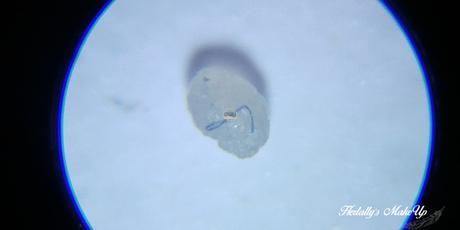

En la primera imagen podéis observar la etiologia de mi ya extirpado amigo: un pelo enquistado.

La verdad es que en su momento me sorprendió muchísimo, ya que no asociaba la ojera con una zona donde hubiese pelos que se pudiesen enquistar.

En esta segunda imagen comparo el millium con la punta de la aguja que usé para sacarlo (diámetro: 18G). Siento que esta esté un poco "sucia", pero no os podéis imaginar lo difícil que fue hacer esta foto en concreto.